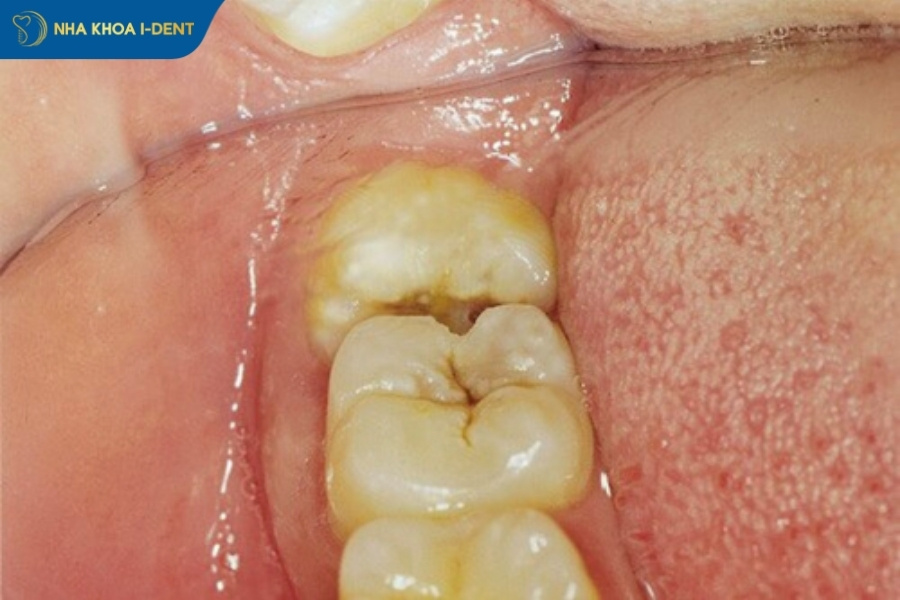

- Gây sâu răng số 7 và các răng lân cận do răng khôn mọc lệch đâm vào răng số, tạo khe giắt thức ăn khó vệ sinh.

- Gây hôi miệng vì răng khôn mọc lệch khó vệ sinh, gây giắt thức ăn làm tích tụ vi khuẩn dẫn đến viêm nướu, lợi trùm và chảy mủ.